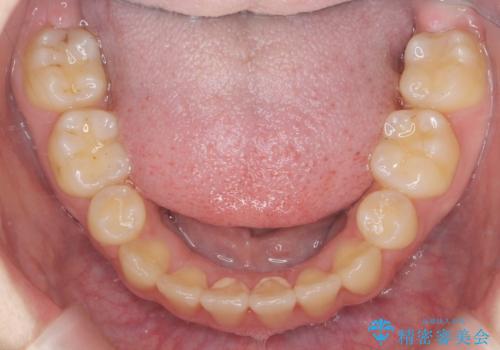

治療後は非常に歯ブラシがしやすくなったと、治療結果に満足いただくことができました。

- 歯並びのがたつきにより歯ブラシがしづらく、今後虫歯になってしまう不安から、矯正治療を希望されて来院されました。

歯を並べるにはスペースが不足しているため、小臼歯の抜歯を4本行うマルチブラケット矯正による治療を計画します。